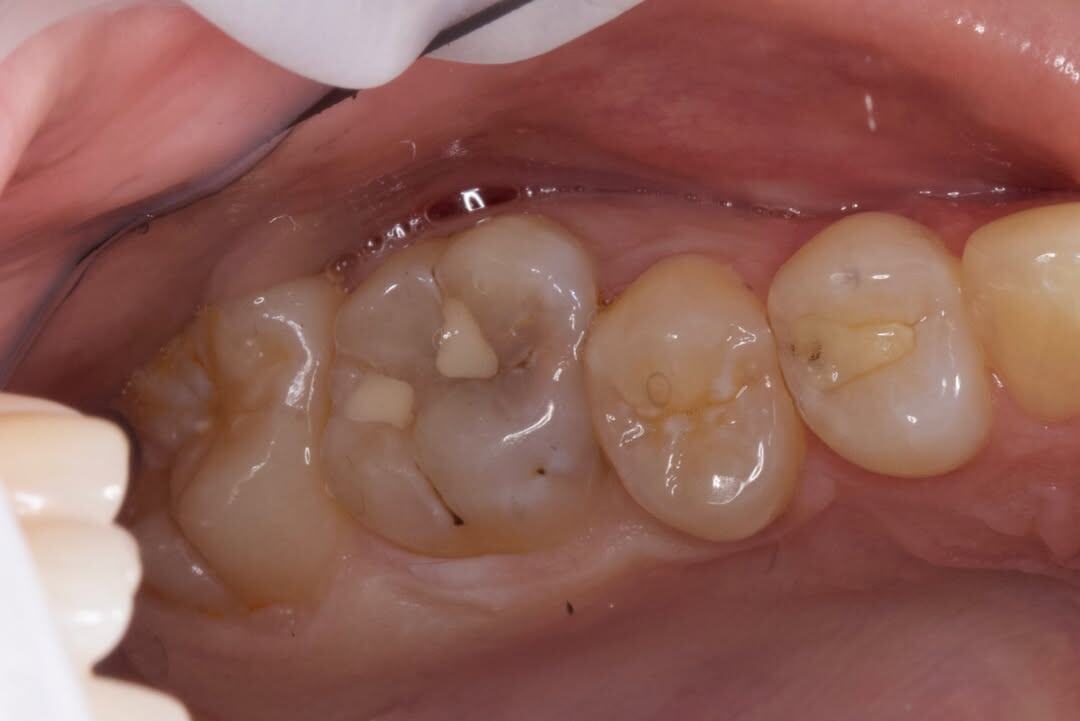

Клинический случай: запущенный кариес

История одного зуба наглядно показывает, почему не стоит откладывать лечение кариеса.

Запущенный кариес = лечение каналов, а еще бывают случаи, когда запущенный кариес приводит к удалению зуба 💡

На фото - работа доктора Аманды Дадаевны.